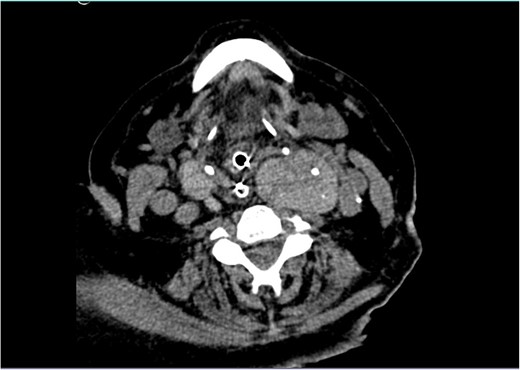

The patient remained monitored but a few hours later progressed with stridor and aggravated hypoxemia. An urgent nasopharyngoscopy was performed which showed significant laryngeal oedema and bulging of the posterior wall of the left hypopharynx. Despite systemic corticoid therapy, a decreased level of consciousness and desaturation lead to an orotracheal intubation. An urgent neck CT revealed a large multinodular goitre (RL 46 × 36 × 91 mm and LL 48 × 51 × 103 mm), with the superior pole of the left lobe ascending to the angle of the mandible, in a suprahyoid position, posterior to the submandibular gland (Fig. 1). The thyroid was extrinsically compressing the trachea and larynx, causing a deviation of the respiratory column to the right and narrowing of its lumen (Fig. 2). There was no apparent invasion of adjacent structures.

Neck CT showing a large goitre with extension to the left angle of the mandible.